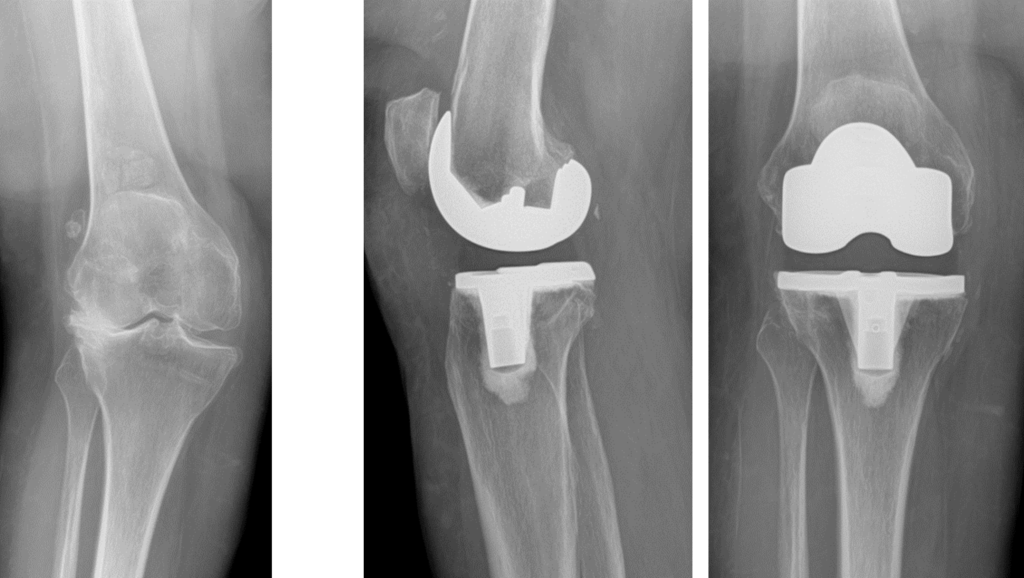

Bone surfaces at joints (such as the hip, knee, or shoulder) are covered by a smooth tissue called cartilage which allows the surfaces to move against each other while providing protection to the bone ends. Arthritis (also called degenerative joint disease) is a condition where this cartilage wears away and changes begin taking place within the joint (figure 1). As cartilage degeneration occurs, pain can develop which can be severe and functional limitations can result.

Knee replacement is a surgery whereby the surfaces of the knee joint are replaced by artificial surfaces (commonly metal and plastic parts). The arthritic surfaces of the femur (thigh bone) and tibia (shin bone) at the knee are removed and replaced with metal load bearing surfaces. A plastic liner that will fit onto the new metal tibial surface and articulate with the new artificial metal surface on the femur is inserted as well (figure 2). A plastic (or metal and plastic) piece may or may not be used to resurface the patella (knee cap) depending upon how much arthritis is present in this part of the joint.